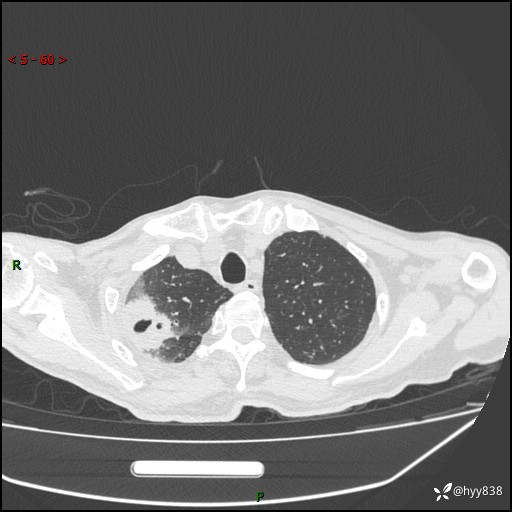

第一次胸部CT检查